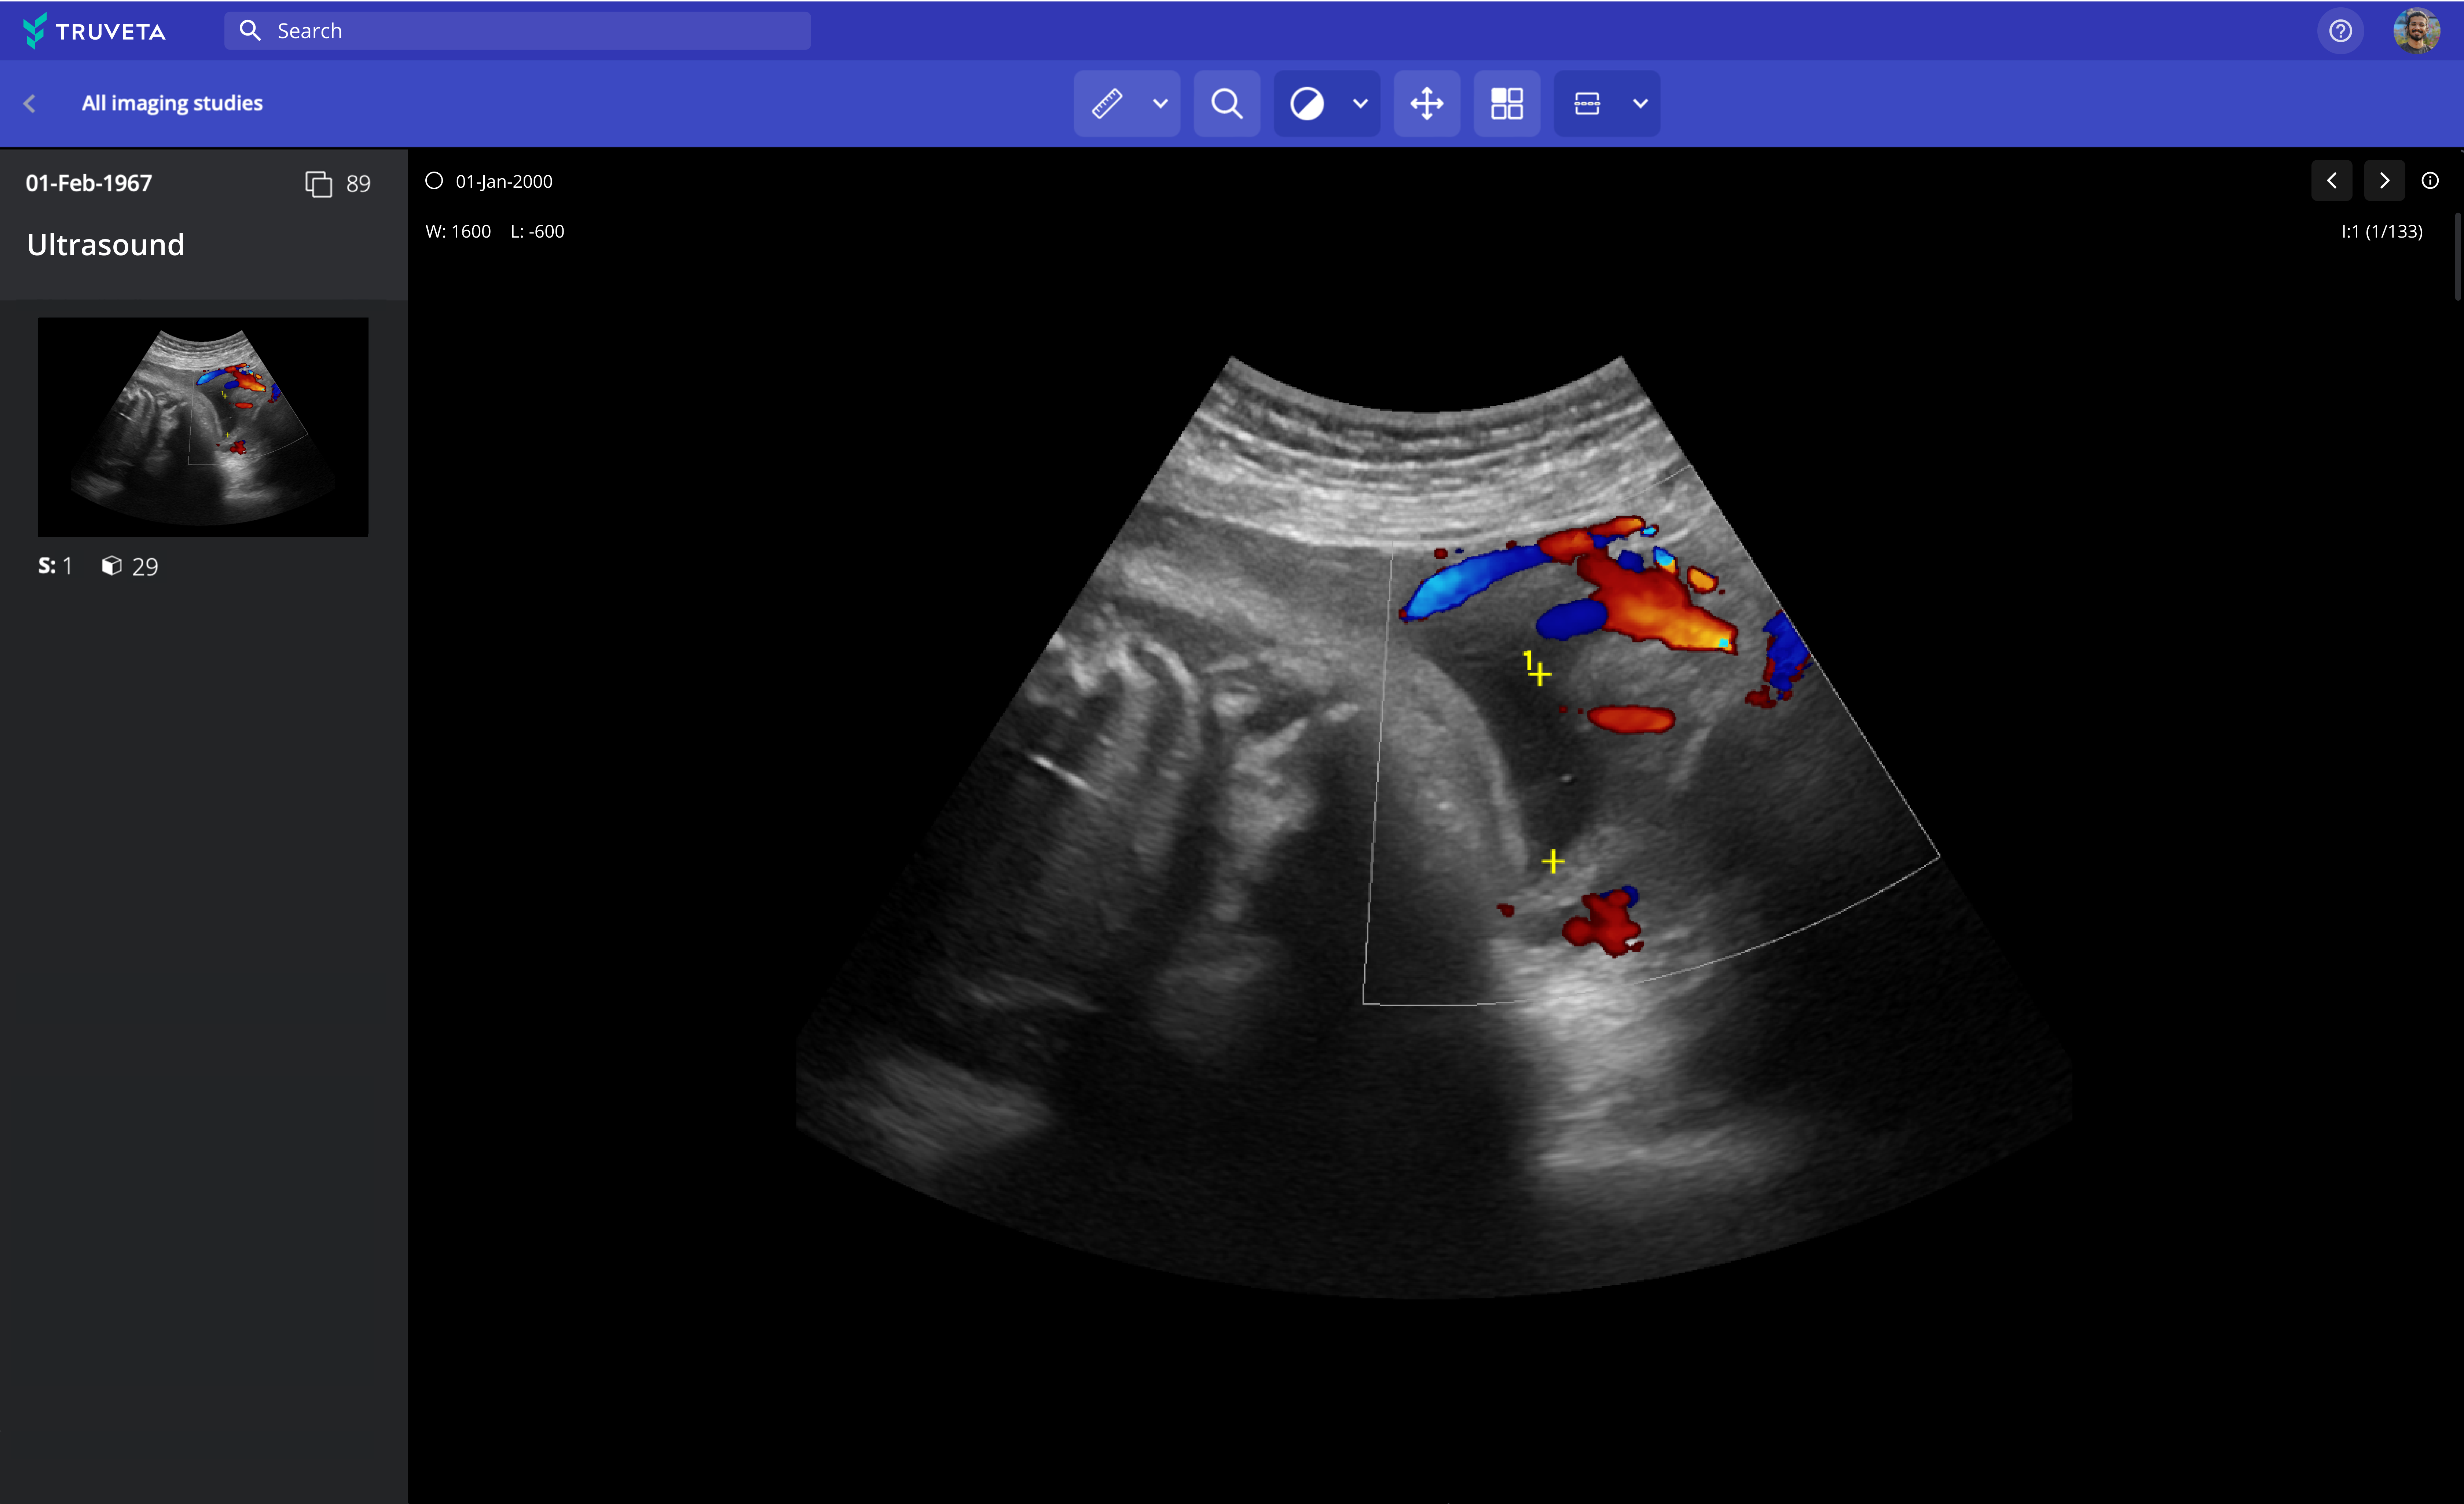

The largest and most complete medical image dataset

Valuable information about patients is available in images and their associated metadata, but isn’t routinely captured in real-world datasets. And, the rarer the condition, the more difficult it is to find de-identified images to deepen research on that condition.

Truveta now empowers researchers to learn from millions of de-identified medical images – across all modalities, including MRI, CT, X-ray, ultrasound, mammogram, and nuclear medicine – integrated with the patient’s EHR data to more deeply understand symptoms, diagnoses, disease progression, and more. Over 85 million imaging studies include 39 million digital X-rays, 14 million ultrasounds, 16.5 million CT images, 5.2 million MRI images, 500,000 nuclear images, and 10 million mammograms. Medical images are updated daily, cleaned with clinical expert-led AI, and de-identified with industry-leading privacy and security technology.

Truveta Data includes complete metadata on each image, such as the size, dimensions, bit depth, modality used to create the data, and equipment settings used to capture the image. These raw pixel data, which are not found in the EHR or in clinical notes, are required to build intelligent AI/ML algorithms that can interpret images and be used to enable point-of-care diagnoses within medical devices, as well as automate and accelerate clinical research and development.

A new imaging viewer in Truveta Studio enables researchers to view thousands of images at a time, including single view or multi-view, with built-in annotation tools for marking up images, enabling researchers to view the images associated with their patient populations, and even export them for training algorithms for diagnostics, peer-reviewed research, or regulatory filings. Images can be analyzed in notebooks in Truveta Studio and included in studies for scientifically rigorous research.

By directly integrating imaging and pixel data with complete patient medical records, Truveta bridges critical evidence gaps and elevates patient insights, ultimately leading to improved patient outcomes.